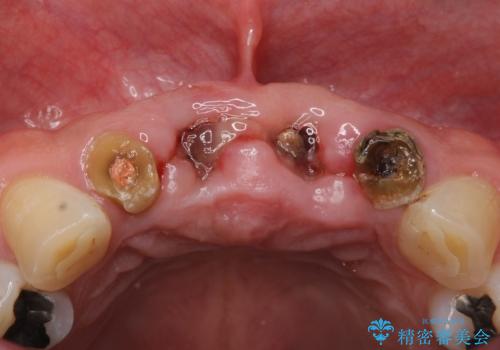

- お風呂場で転んで上の前歯が2本抜けてしまったことを主訴に来院された患者様です。

精査したところ、左上の側切歯(左上2)も破折しており保存不可能な状態でした。

左上の側切歯(左上2)を抜去し、右上の側切歯(右上2)の再根管治療後、セラミックのブリッジによる補綴を行いました。